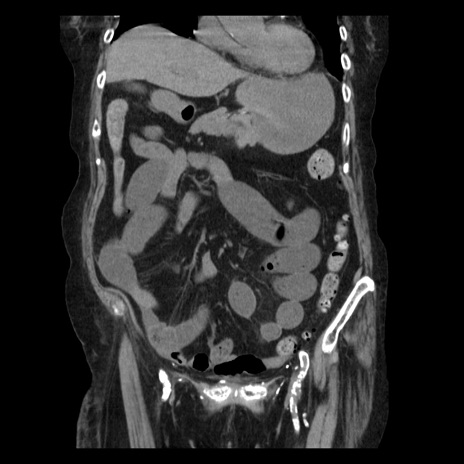

症例14(冠状断像)

【症例】 90歳代女性

【主訴】 腹痛・嘔吐

【現病歴】今朝から左側腹部痛を認めた。 経過観察していたが、嘔吐を認めたため来院。

【既往歴】 子宮癌術後

【身体所見】 意識清明、BP 127/54mmHg、P 98bpm Sp02 95%(RA)、BT 35.8°C、腹部平坦・軟腸ぜん動音聴取良好、右下腹部圧痛(+) 反跳痛なし

【データ】WBC 9800、CRP 0.46